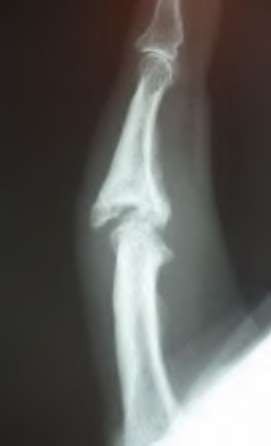

A 35-year-old woman reports wrist pain after a fall onto an outstretched hand. On exam, she has focal tenderness over the wrist snuffbox. A radiograph and CT image are shown in Figures A and B. What is the proper treatment of her injury?